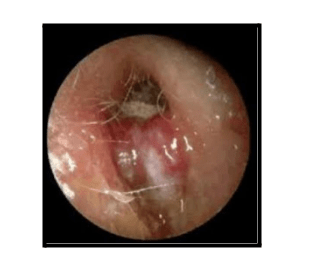

- Granulation tissue in the ear canal

Granulation in the external ear canal may also occur, which is more common in individuals with diabetes. Diabetes affect ear, increasing the risk of developing conditions like necrotizing otitis externa.

The diagnosis is primarily clinical, based on symptoms and signs, along with radiological findings from a CT scan. In cases where infection is suspected, a culture of pus (a sample of the discharge) from the ear or a biopsy of the granulation tissue from the external ear canal may be required. Diabetes affect ear by making individuals more susceptible to infections, such as Necrotizing Otitis Externa (NOE), which can complicate the diagnosis.